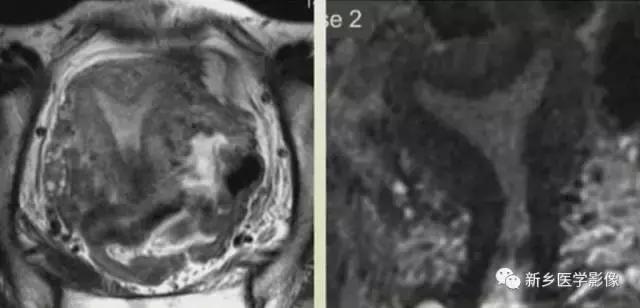

上图:单角子宫(II-B残角,有内膜腔,不相通):右侧残角宫腔内积血,为短T1长T2异常信号。左侧单角子宫,见带状结构,呈香蕉样。